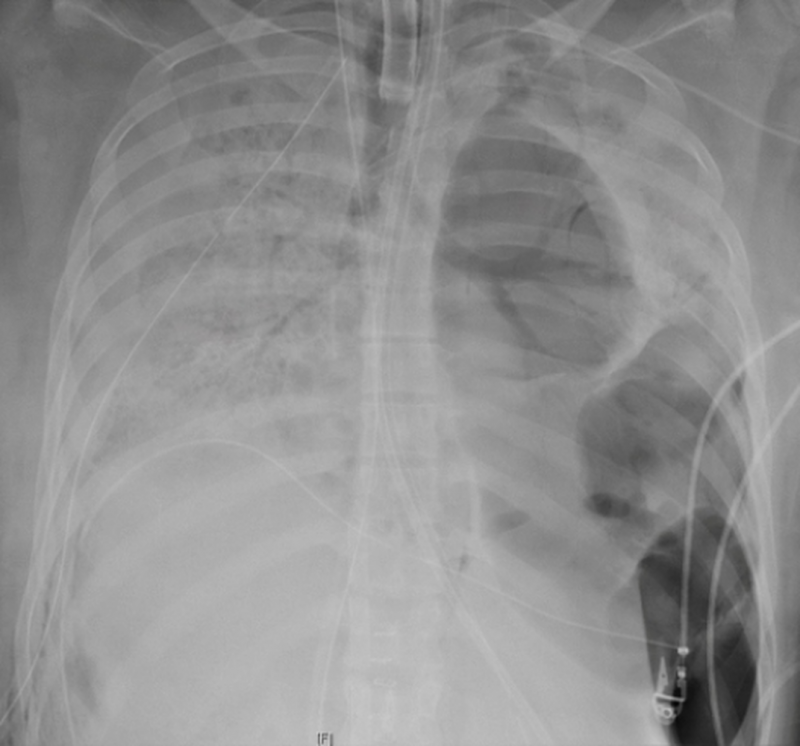

Así se ven los pulmones de un paciente con coronavirus A finales de marzo, el Hospital de la Universidad George Washington alertaba sobre la inflamación pulmonar ante el covid-19 y los daños irreparables que podía provocar.

"Cuando esa inflamación no disminuye con el tiempo, se convierte esencialmente en cicatrices en los pulmones, creando daños a largo plazo… Podría afectar la capacidad de alguien para respirar a largo plazo", explicaba el doctor Keith Mortman, jefe de Cirugía Torácica en el Hospital GW.

El GW Hospital está utilizando la tecnología de Realidad Virtual (VR) en la lucha contra covid-19. La tecnología VR permite al equipo médico ver los pulmones del paciente afectado por el coronavirus. "Existe un marcado contraste entre el pulmón anormal infectado por el virus y el tejido pulmonar adyacente más saludable", dijo el Dr. Mortman.

"Y es un contraste tal que no necesita una especialidad para comprender las imágenes. Esto es algo que el público en general puede analizar y realmente comenzar a comprender qué tan grave es la cantidad de daño que está causando el tejido pulmonar. El daño que estamos viendo no está aislado en ninguna parte del pulmón. Es un daño severo en ambos pulmones de manera difusa", explicaba.